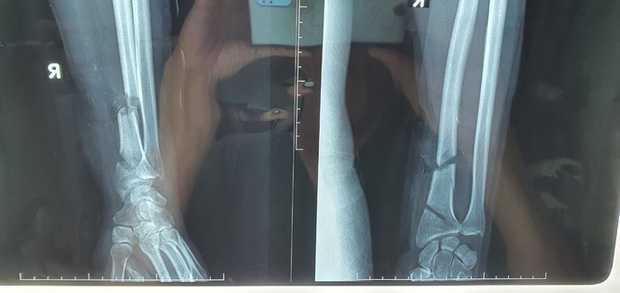

09/12/2020 20:41Dùng máy cưa tỉa cây, người đàn ông bị cắt đứt gần lìa cổ tay và cổ chân

Ngày 9/12, Bác sĩ CK2 Phạm Thanh Phong - Phó Giám đốc phụ trách chuyên môn Bệnh viện Đa khoa Trung ương Cần Thơ cho biết, các bác sĩ Trung tâm Chấn thương chỉnh hình của bệnh viện vừa phẫu thuật thành công một trường hợp tai nạn lao động rất nguy kịch, bệnh nhân bị máy cưa cắt đứt gần lìa cổ tay 2 đoạn và cổ chân.

Bệnh nhân nói trên là ông N.N.P.V (62 tuổi, ngụ quận Ninh Kiều, TP. Cần Thơ). Sau tai nạn lao động do sử dụng máy cưa tỉa cây cảnh, ông V. được đưa đến bệnh viện cấp cứu trong tình trạng cổ tay phải đứt gần lìa 2 đoạn, bàn tay tím tái, đau nhức dữ dội, lộ gân xương, không cử động được các ngón tay, kèm vết thương phức tạp cổ chân trái.

Ekip phẫu thuật vi phẫu và chấn thương đã tiến hành vi phẫu thuật sử dụng kính hiển vi phẫu thuật có độ phóng đại từ 8 - 25 lần để phẫu tích và khâu nối bằng kim chỉ loại cực nhỏ, khâu nối chính xác các mạch máu nhỏ có đường kính ≈ 1mm và các bao bó sợi thần kinh.

Vết thương vùng cổ tay phải 2 đường cắt khoảng 2/3 chu vi cổ tay, đứt gần hết mạch máu, gân cơ và thần kinh. Trong đó, xương quay và một số gân cơ, mạch máu vùng cổ tay đứt 2 đoạn.

Đặc biệt động mạch quay đứt 2 đoạn, dập nát không thể khâu nối như bình thường, các bác sĩ phải lấy tĩnh mạch ở nơi khác để ghép vào thay đoạn động mạch dập nát. Tổn thương xương quay bên phải được cố định bằng Kirschner. Vết thương vùng cổ chân trái 6cm, đứt toàn bộ gân gấp, gân gót, mạch máu thần kinh, được tiếp tục khâu nối mạch máu, thần kinh và gân gót. Trước vết thương phức tạp này, các bác sĩ đã phải phải huy động cùng lúc 2 ekip vi phẫu để chạy đua thời gian phẫu thuật cho bệnh nhân.

Sau hơn 5 giờ phẫu thuật căng thẳng, bàn tay bệnh nhân hồng trở lại. Hiện tại, các ngón tay bệnh nhân hồng, sờ mạch rõ, các ngón tay cử động được, vết thương cổ chân ổn định, có thể khẳng định bước đầu giữ lại bàn tay cho bệnh nhân gần như đã thành công. Tuy nhiên bệnh nhân cần điều trị tích cực để tránh nhiễm trùng, lành xương và tập vật lí trị liệu để phục hồi chức năng bàn tay.